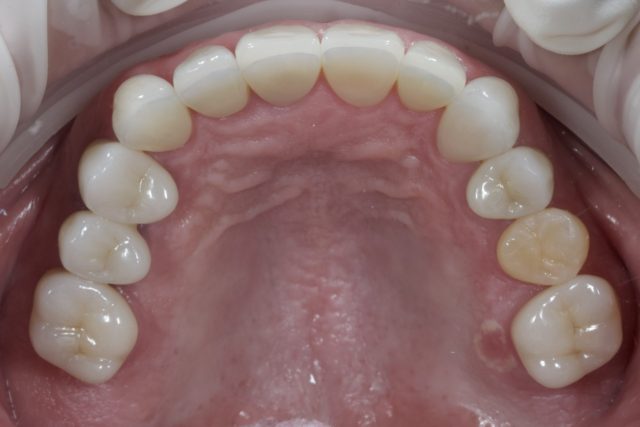

口腔内全体の治療

| 症状 | 口腔内全体の治療を希望されて来院 |

|---|---|

| 治療法 | 両側下顎4.5.6インプラント 天然歯17本補綴 矯正治療 |

| 費用 | 合計約600万円 |

| 通院回数 | 期間約1年半、通院30回程度 |

| 備考 | 全体で問題が起こり機能が失われた状態をトータルでマネジメントし元あった理想に近い形に戻すことを行なっているが、これにはかなりの時間と費用がかかり、大変な治療に耐えていただく必要がある。 また全ては修復物や補綴物やインプラントで見た目と噛む機能を整えているに過ぎず、実際には歯が再生したわけではない。強度の落ちている歯をよく噛める形に整えるという事は、歯が壊れる可能性も同時に上げることになる。つまり施した治療が必ずしも一生保つという事ではない。 よって可能な限りこの状態を長く保つことが出来るよう、治療後は定期的なメンテナンスと、ナイトガード(寝ている間の歯軋りや食いしばりなどの自身でコントロールできない過剰な力から歯を守るマウスピース)の装着が必須となる。 |